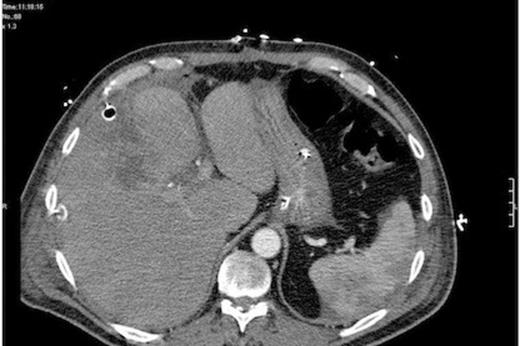

Post-operatively the patient was ventilated, continued on broad spectrum antibiotics, transfused packed red cells, fed parenterally initally, and haemofiltered for acute renal failure. Ventilatory and inotropic support were able to be weaned quickly and the jaundice improved over the following week. The abdominal drains were removed sequentially once dry.

Repeat CT post-laparotomy and lavage showing large bore peritoneal drains